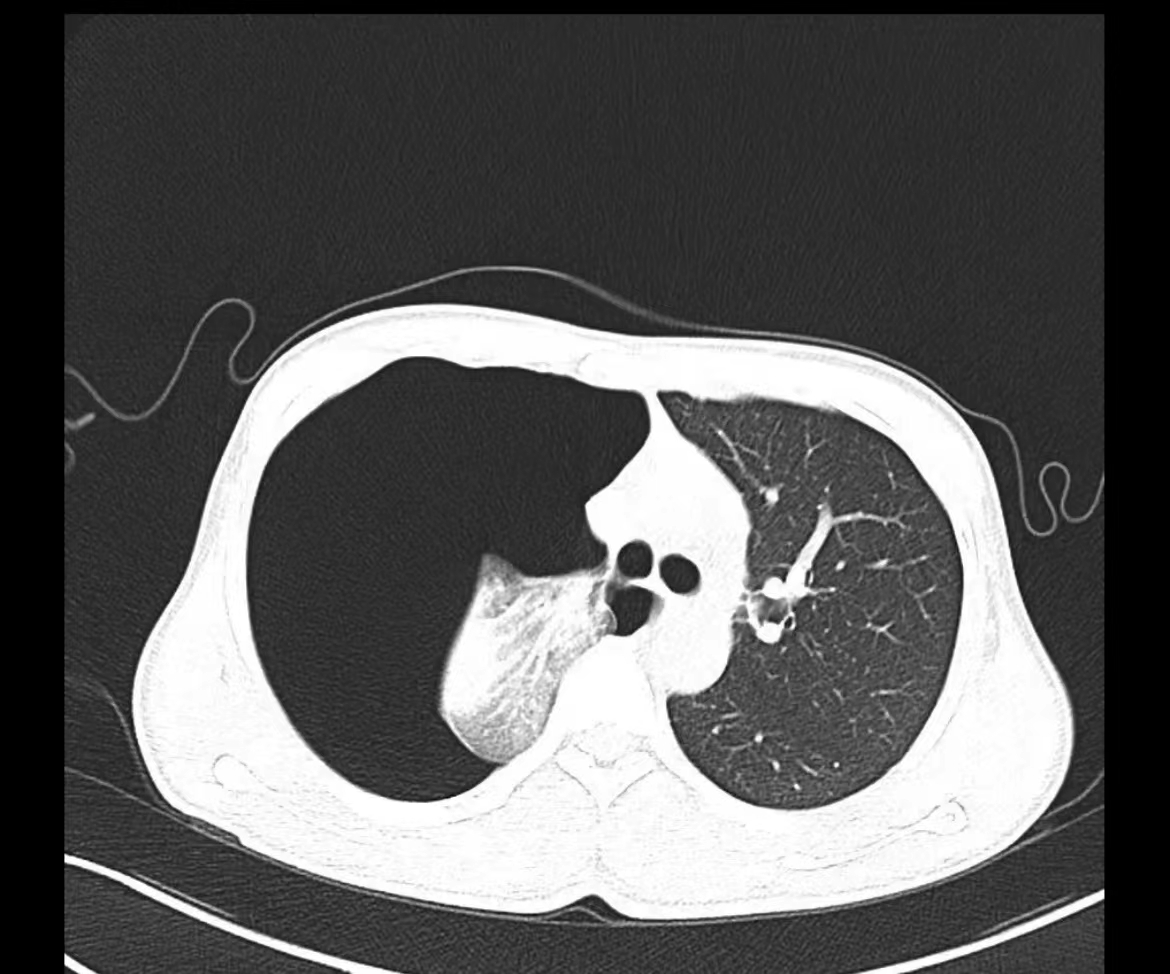

夜班急诊来了一位老大娘,捂着胸口来到CT室说:“医生,快帮我检查一下吧,看我出了什么毛病,胸口痛得厉害,出气都可疼,还闷得慌!”。于是立马登记完检查信息、赶紧给她进行CT扫描,结果一看是气胸,图像如下:

老大娘下了扫描床便说:“都怪我家那儿子,30好几了还不结婚,还没说他两句还给我顶嘴,给我气得直哆嗦,然后我就开始这样了”。看来肺还真能被“气炸”了啊!